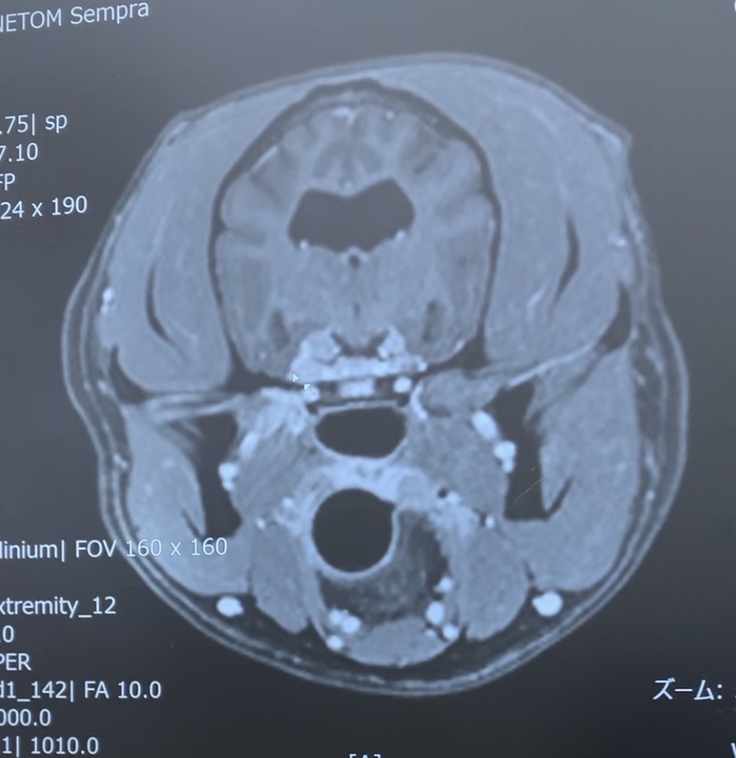

2025年5月2日

神経科の専門医がいる2次診療の高度医療病院を受診。

⇒MRI検査となりました。

一過性のものである事を祈りながら待ちましたが、MRI検査結果は脳に腫瘍があるというとても辛く悲しい現実でした。

診断名

【リンパ腫 動眼神経・三叉神経】

これが目の違和感の理由でした。

また、脳という事もあり、定期検診には全身麻酔が伴うMRI検査やCT検査が含まれます。

▶︎上記に加え、定期的なMRI検査

1回193,340円(税込)

(↑頭部のみの場合の金額)

定期検診では全身のMRIとなる為、更に高額医療費になります。